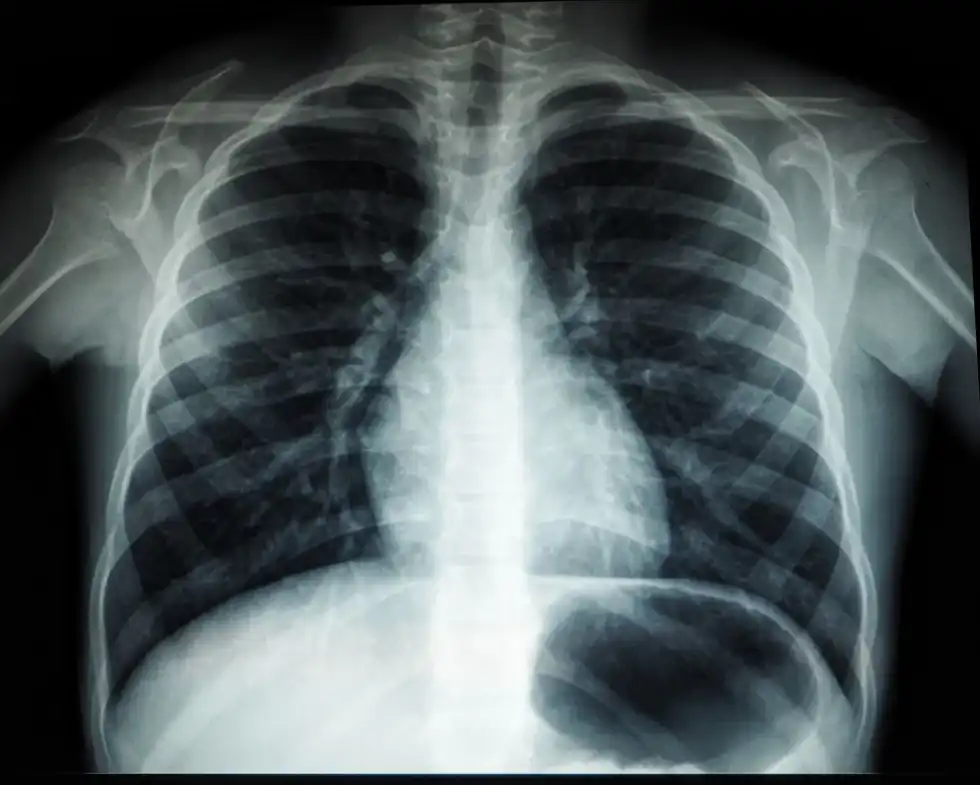

An arthrogram is useful to find arthritis with joint alterations, malignancy in bones, and osteoporosis by measuring bone density. Pneumonia, lung cancer, and tuberculosis can be identified through chest x-rays. Lymphoma in breasts with mammography, heart issues with any conversion in blood flow, and digestive tract issues like kidney stones, and accidentally swallowed objects can also all be identified.

Iodine-based contrast dyes are common when you are tested in arthrogram to identify if you have bursitis or shoulder issues. Barium-based dyes have their use during fluoroscopy.